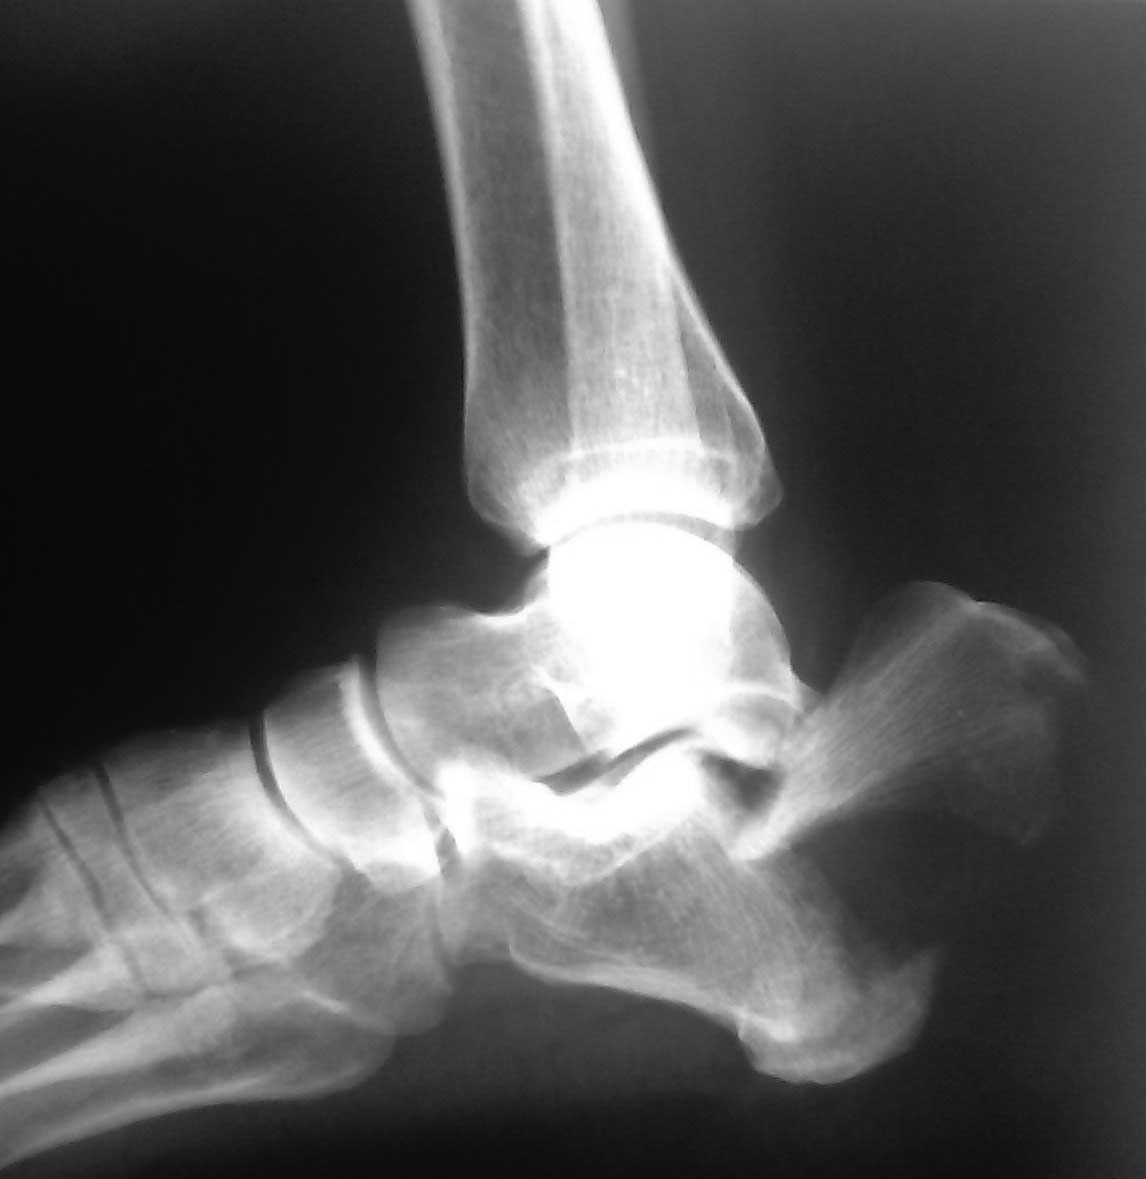

перелом пяточной кости

пациент 1966г.р. травма бытовая 19.06.12г падение с высоты 2 этажа, находясь в состоянии возбуждения, на фоне отмены алкоголя. Пациент галлюцинировал, была наложена гипсовая лонгета, госпитализирован в наркологическое отделение. После вывода из состояния возбуждения был переведен в травматологическое отделение. Определялся выраженный отек пяточной области, обширные фликтены. Наложено скелетное вытяжение за пяточный бугор, которое пациент самостоятельно неоднократно снимал ( отрывал шнур и снимал груз). Скелетное вытяжение несколько раз переводилось, пациент ходил с полной нагрузкой на больную ногу . Проводилась закрытая ручная репозиция- безуспешно.в настоящее время флектены зажили, по задней поверхности в области пяточного бугра определяется участок некроза ( следствие пролежня от отломка), черного цвета без явных признаков воспаления, 3.3*3.5 см).планируем открыться(хотя настораживает наличие некроза), попытаться выполнить репозицию ,вопрос встал чем фиксировать, в наличии есть только аппарат, винты, пластин нет. Заранее спасибо. С уважением Роман Д.